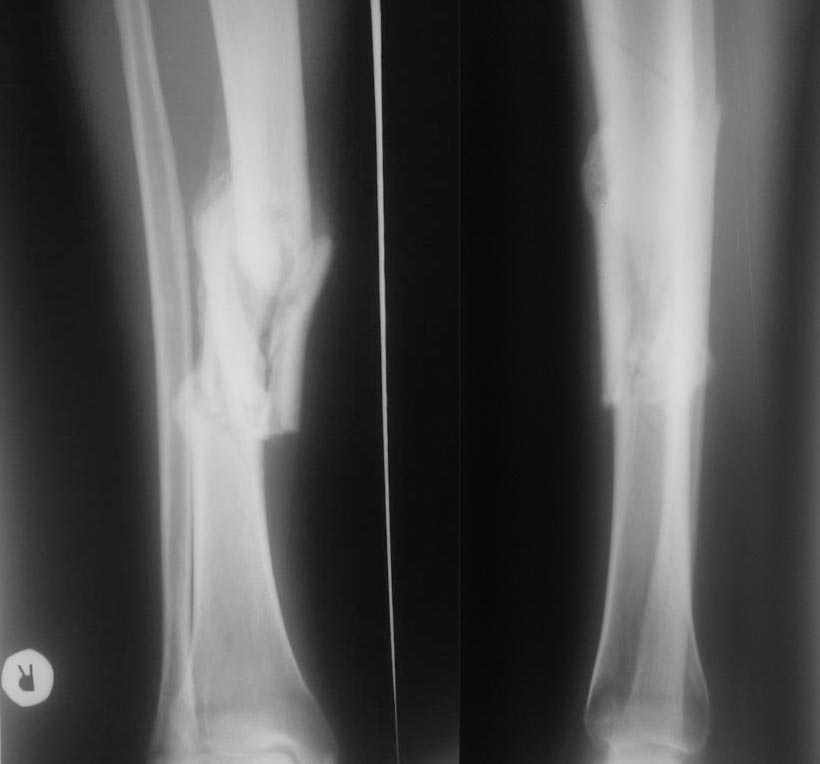

Re: Неправильно сросшийся перелом голени.

Уважаемый Алексей! Я бы сделал для начала Р-граммы всей голени с захватом обоих суставов и оценил бы ось сегмента. И потом, что за больной, возраст, сопутствуюшие заболевания и повреждения, и вообще - чего хочет пациент. Если бы оперировать "картинку", то сначала исправил бы ось в аппарате и затем закрыто заштифтовал.Так вот в общих чертах... Подобные случаи на форуме неоднократно обсуждались.

и механическая, и анатомическая оси сегмента однозначно смещены. для определения степени нужны адекватные снимки как ранее сказано. правильные снимки в студию. Ортопедический случай все-таки.

Я бы оценил эту ситуацию как неправлиьно СРАСТАЮЩИЙСЯ перелом.

По поводу " неправильно срастающийся" - некорректная формулировка. Может быть - с неустраненным смещением? А "срастающийся" - это уже хорошо. Не все переломы срастаются. Дело не в том. По моему мнению - не мешайте природе, если вовремя не вмешались. Хотите помочь - наложите аппарат, потяните с учетом коррекции деформации и укорочения конечности. Устраните смещение - дальше появляются варианты - оставить в аппарате или фиксировать другим способом. Решать Вам. Если в аппарате смещение не устранится - ничего страшного, главное - достичь сращения и восстановления опорнй функции конечности, не такая уж и грубая деформация. Ортопедические моменты можно оставить на "потом".

Если оставить в нынешнем виде, вероятность патологической перестройки будет высокая.

Более целесообразно аппарат в дистракционном режиме, с репозицией спицами с напайкой.